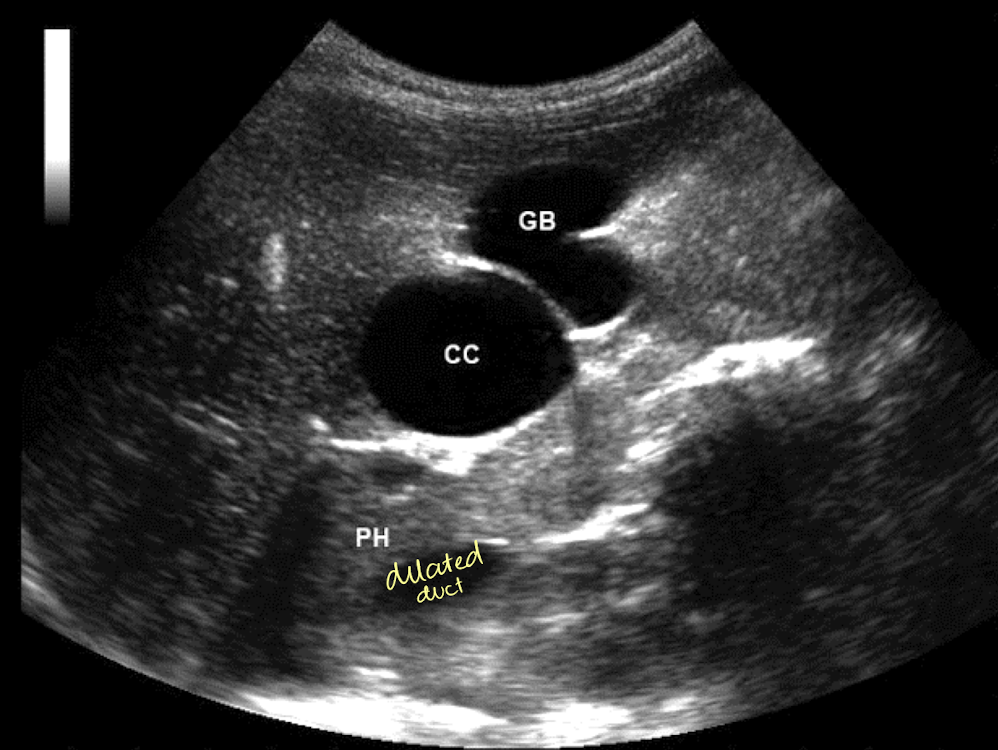

SONO: Caroli’s disease

multiple cystic structures in the track of ducts (in the area of the ductal system) that converge at portal hepatitis

“Central dot” sign = dilated duct surrounding the adjacent HA and PV

one Mickey ear is bigger than the other

??

Type 5 choledochal cysts (Caroli’s disease)